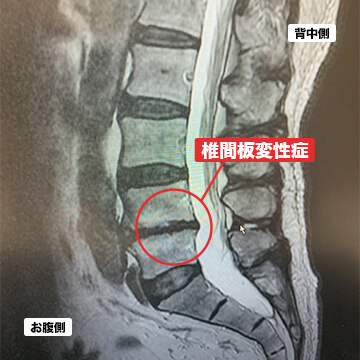

- 椎間板変性症

椎間板変性症とは、椎間板と呼ばれる組織に傷が入り、中の髄核が漏れ出して硬くなることで椎間板が変形してしまう状態を言います。変形が進行すると椎間板ヘルニアになることもあります。主に腰痛の症状が多いとされています。